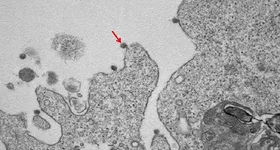

Imaginile pe care le-au prezentat cercetătorii din cele două țări au fost realizate cu ajutorul microscopului electronic în care este surprins atât coronavirusul SARS-COV-2 ce produce boala COVID-19, cât şi celulele infectate şi răspunsul sistemului imunitar.

Astfel, după cum se poate observa în imaginile care au fost colorate, SARS CoV-2 are în exterior o “coroană de țepi”. De altfel, de aici îi vine numele. Aceştia se prind de o enzimă umană numită ACE2, iar compatibilitatea dintre țepișorii virusului și enzima umană este extrem de mare, anunță stirileprotv.ro.